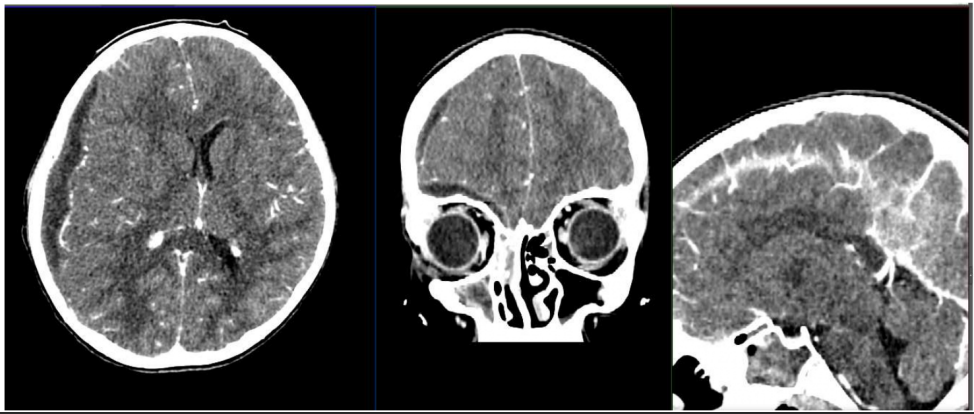

A 8-month-old infant was sent for imaging (figures) by his pediatrician because of irritability, poor feeding, and macrocephaly with a

bulging fontanel. The preceding pregnancy and delivery had been unremarkable. The infant had been well up until this presentation,

and review of systems was noncontributory. What additional diagnostic investigation is indicated?